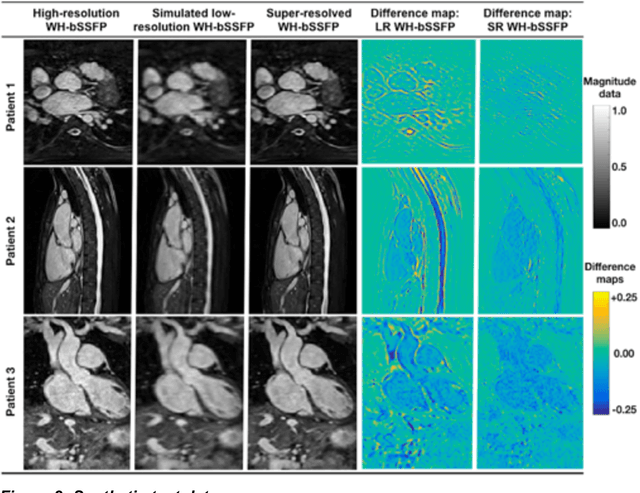

Abstract:Background: Three-dimensional, whole heart, balanced steady state free precession (WH-bSSFP) sequences provide delineation of intra-cardiac and vascular anatomy. However, they have long acquisition times. Here, we propose significant speed ups using a deep learning single volume super resolution reconstruction, to recover high resolution features from rapidly acquired low resolution WH-bSSFP images. Methods: A 3D residual U-Net was trained using synthetic data, created from a library of high-resolution WH-bSSFP images by simulating 0.5 slice resolution and 0.5 phase resolution. The trained network was validated with synthetic test data, as well as prospective low-resolution data. Results: Synthetic low-resolution data had significantly better image quality after super-resolution reconstruction. Qualitative image scores showed super-resolved images had better edge sharpness, fewer residual artefacts and less image distortion than low-resolution images, with similar scores to high-resolution data. Quantitative image scores showed super-resolved images had significantly better edge sharpness than low-resolution or high-resolution images, with significantly better signal-to-noise ratio than high-resolution data. Vessel diameters measurements showed over-estimation in the low-resolution measurements, compared to the high-resolution data. No significant differences and no bias was found in the super-resolution measurements. Conclusion: This paper demonstrates the potential of using a residual U-Net for super-resolution reconstruction of rapidly acquired low-resolution whole heart bSSFP data within a clinical setting. The resulting network can be applied very quickly, making these techniques particularly appealing within busy clinical workflow. Thus, we believe that this technique may help speed up whole heart CMR in clinical practice.